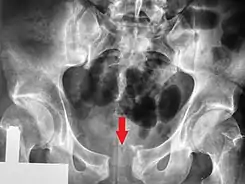

Una radiografía pélvica que muestra una fractura de libro abierto